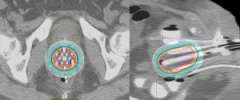

Below is a 3D rendering of the distribution of radiation dose and normal tissues from a gynecologic interstitial implant:

An axial CT slice showing the distribution of small hollow brachytherapy tubes and the distribution of radiation dose for a gynecologic interstitial brachytherapy implant.